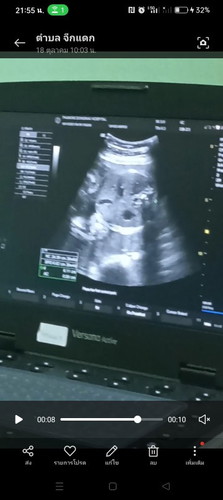

สอบถามผู้รู้คะตรงนี้คือส่วนไหนคะ ตอนนี้28weekเเล่ว

ส่วนหัว กระโหลกคะ